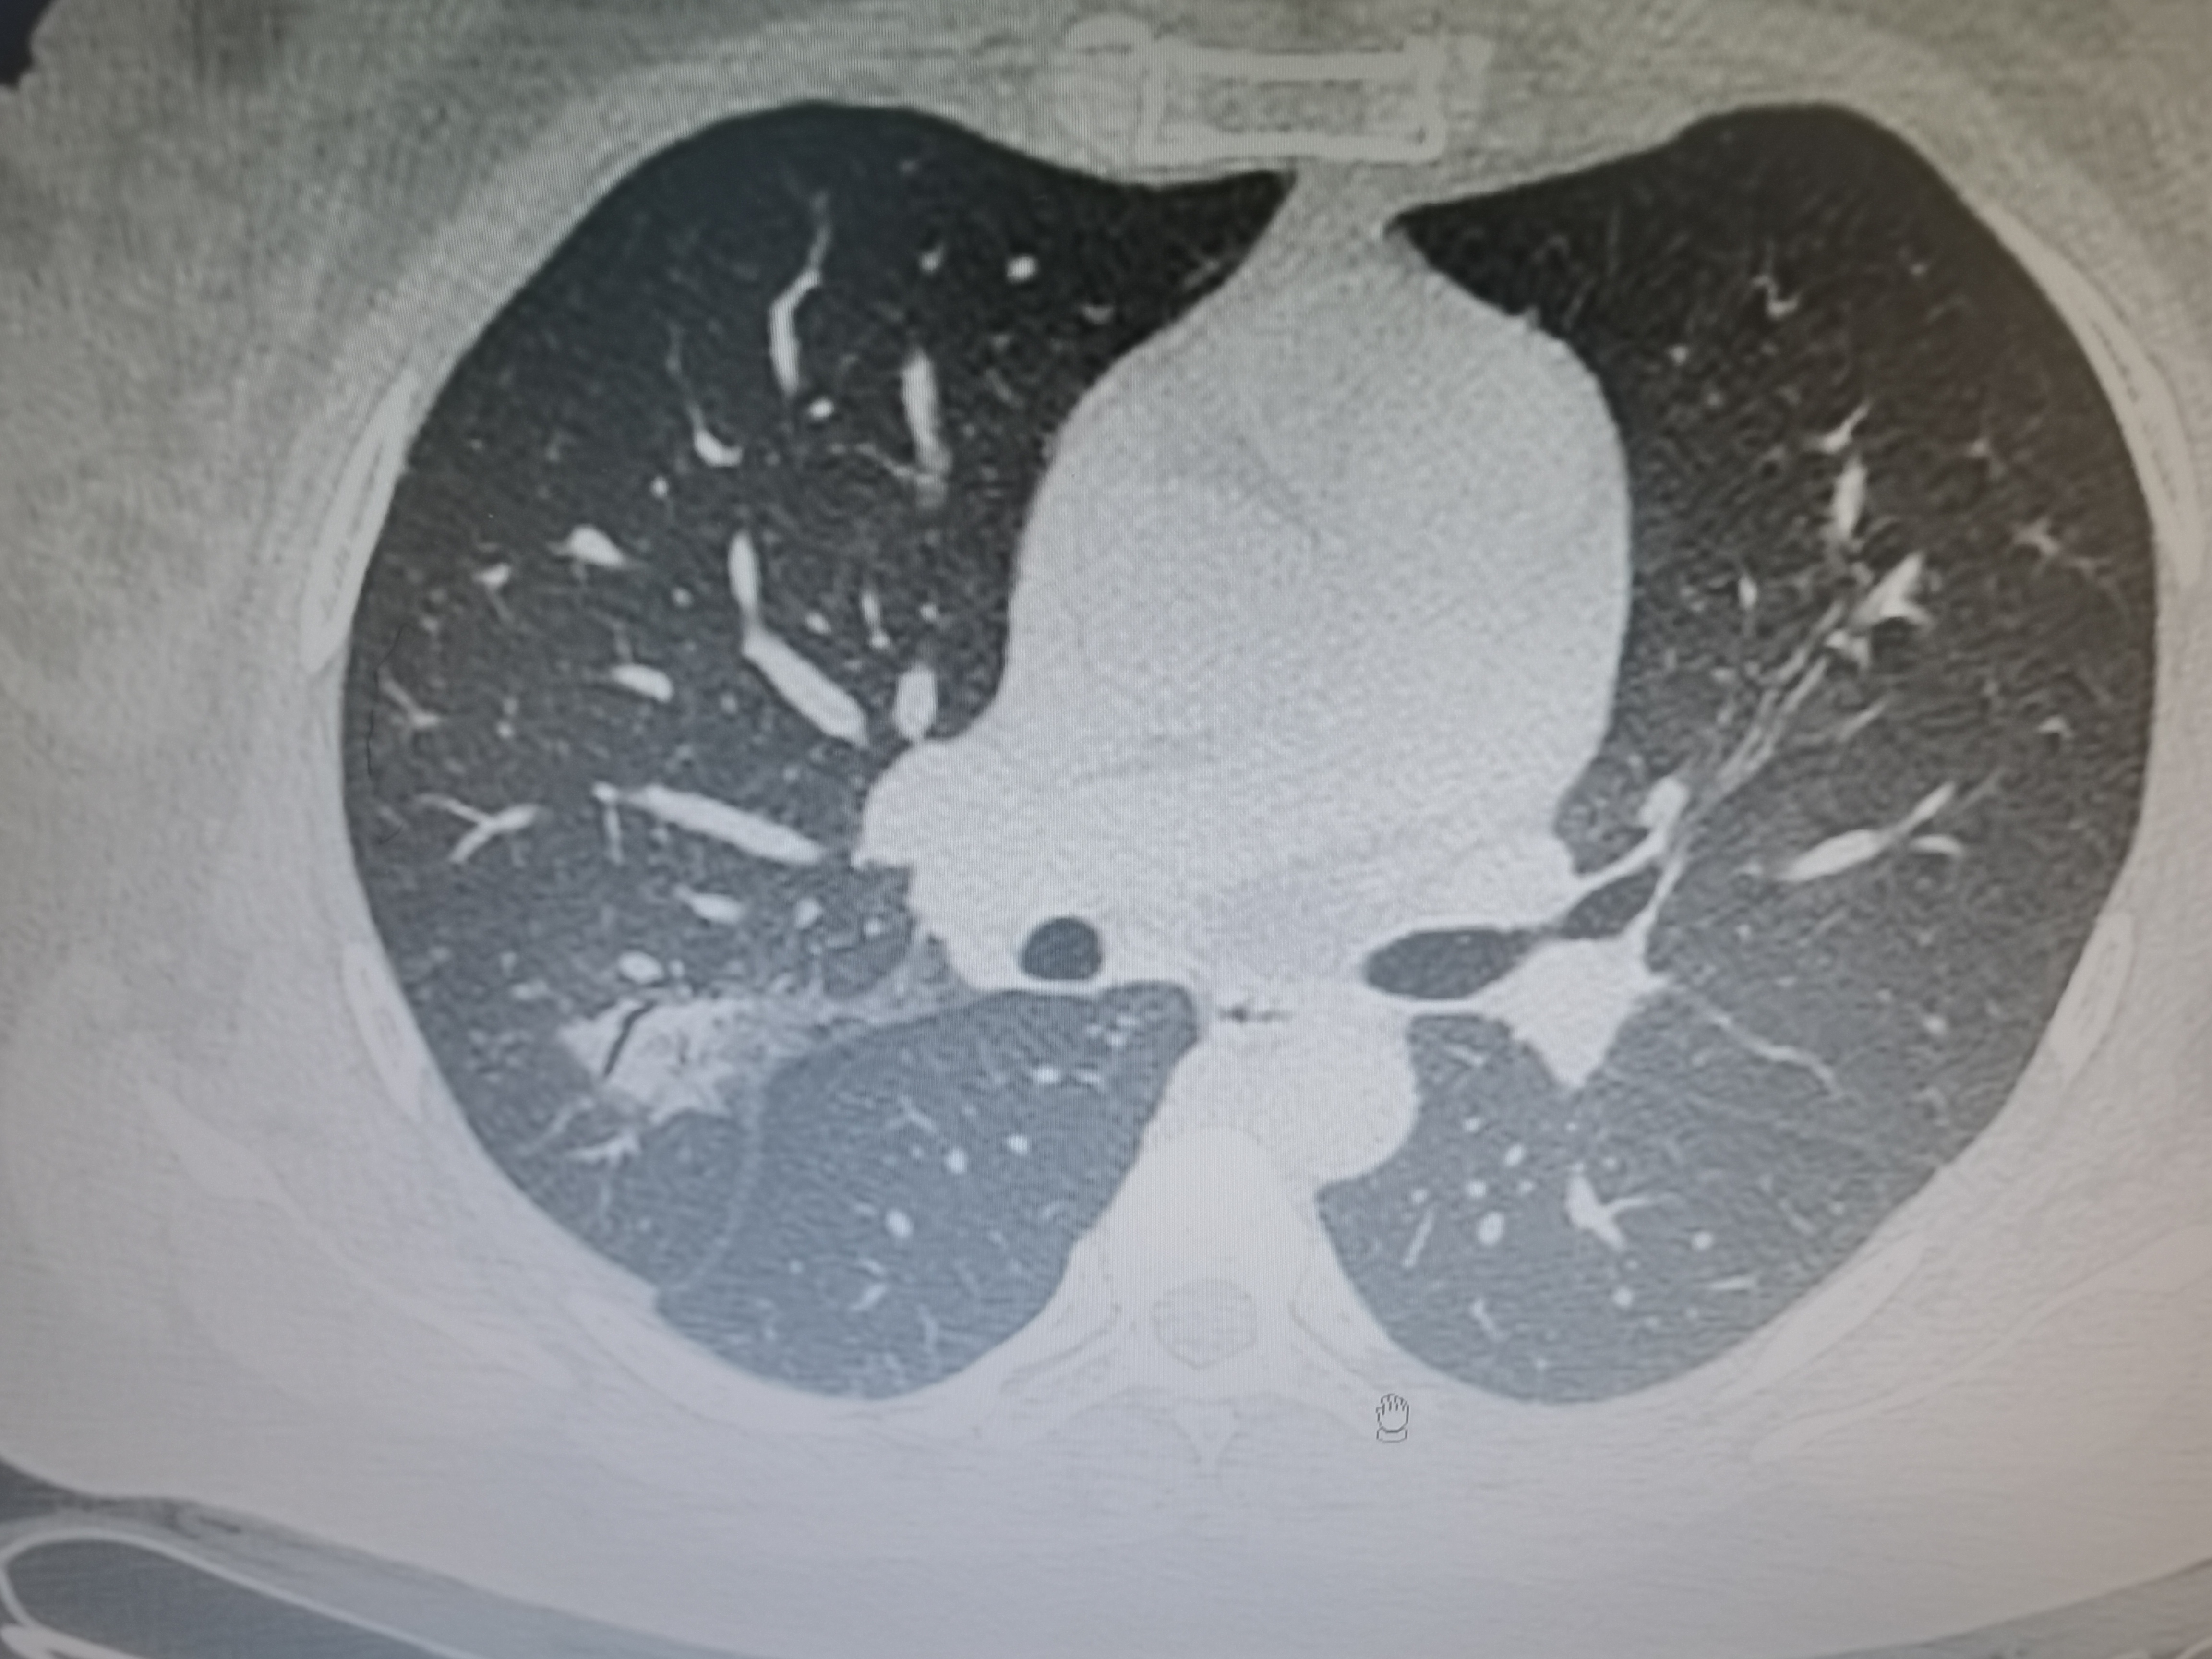

女,63岁,肺粘液腺癌一例